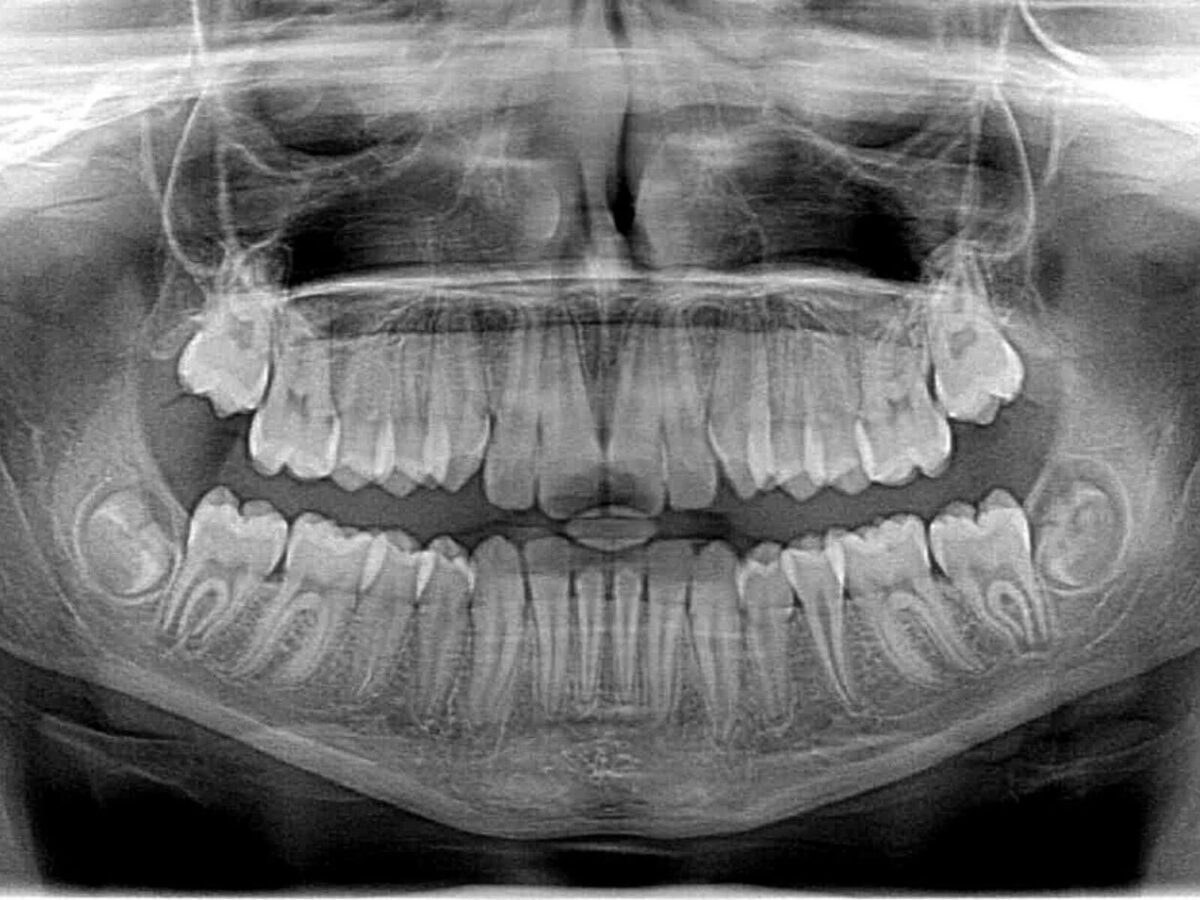

A quick look inside the mouth shows a lot. A mirror and a light reveal stains, broken teeth, and swollen gums. But some problems hide. They sit between teeth, or below the gum line, or under an old filling. Those are the places a clinician cannot see with the eye alone. That is where dental X-rays matter. A Splendora Dentist TX uses them as a routine tool. They give a quieter kind of vision. They show what is hidden, so care is planned with facts, not guesses.

Most folks figure X-rays are only needed when there’s pain or a big problem showing up. The truth is different. X-rays help detect small problems long before they hurt. A tiny cavity between two back teeth appears early on an image. A shadow under a crown shows up before symptoms begin. Even the angle of a root, or a small bone loss next to a tooth, looks clear on a good X-ray.

Cavities that form between teeth hide from a brush and from the eye. They begin inside the contact area, where two teeth touch. An X-ray shows a small dark spot in that space. When clinicians catch that dark area early, a small filling often fixes it. That is a much easier visit than waiting until the cavity reaches the surface and the nerve.

Fillings, crowns, and old restorations sometimes wear or leak. A surface can look fine, yet beneath an old filling, bacteria may have started to decay. X-rays let the clinician see below the surface. They reveal dark lines under a restoration or gaps where cement has dissolved.

Dental problems don’t always start where you can see them. An infection can form near the root tip, or the bone supporting a tooth can slowly shrink. X-rays show changes in bone level and root shape that the eye can’t catch. A small area of bone loss appears as a faint shadow. The clinician notes it and decides whether to watch or act.

Rarely, an image shows something unexpected. A cyst or unusual spot near a root can look like a shadow on the X-ray. Most aren’t serious, but the dentist will monitor them to be sure. When something unusual appears, a Splendora Dental Office TX discusses options. Sometimes imaging alone is enough, sometimes a referral to a specialist is best.